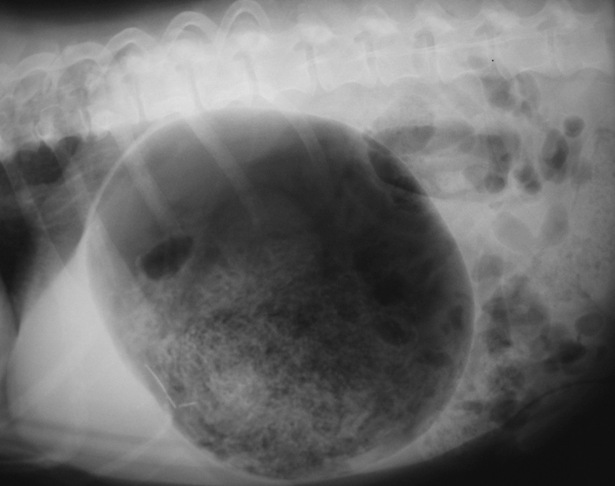

Let’s now discuss how the urethra gets blocked, what it gets blocked with. In the types of cats that we are discussing in this blog, the urethra gets blocked most commonly either with plugs of material including protein, cells and little crystals or with stones formed from minerals that are normally present in the urine. In the normal cat these substances are present in small amounts and pass out in the urine without any problem. However in some cats these substances build up in the urine and then cause an obstruction.

| X-ray from a tomcat showing "stones" (the bunch of little white objects) in the urinary bladder. |

It is possible that lack of enough water in the cat’s food or the cat not peeing often enough can contribute to making this problem more likely. It is important to know that in the types of cats we are discussing here it is actually quite uncommon for there to be a urinary infection present. You should also realise that there are other causes of a blocked bladder, for example a tumour can do this, but also that sometimes we do not find a specific cause.